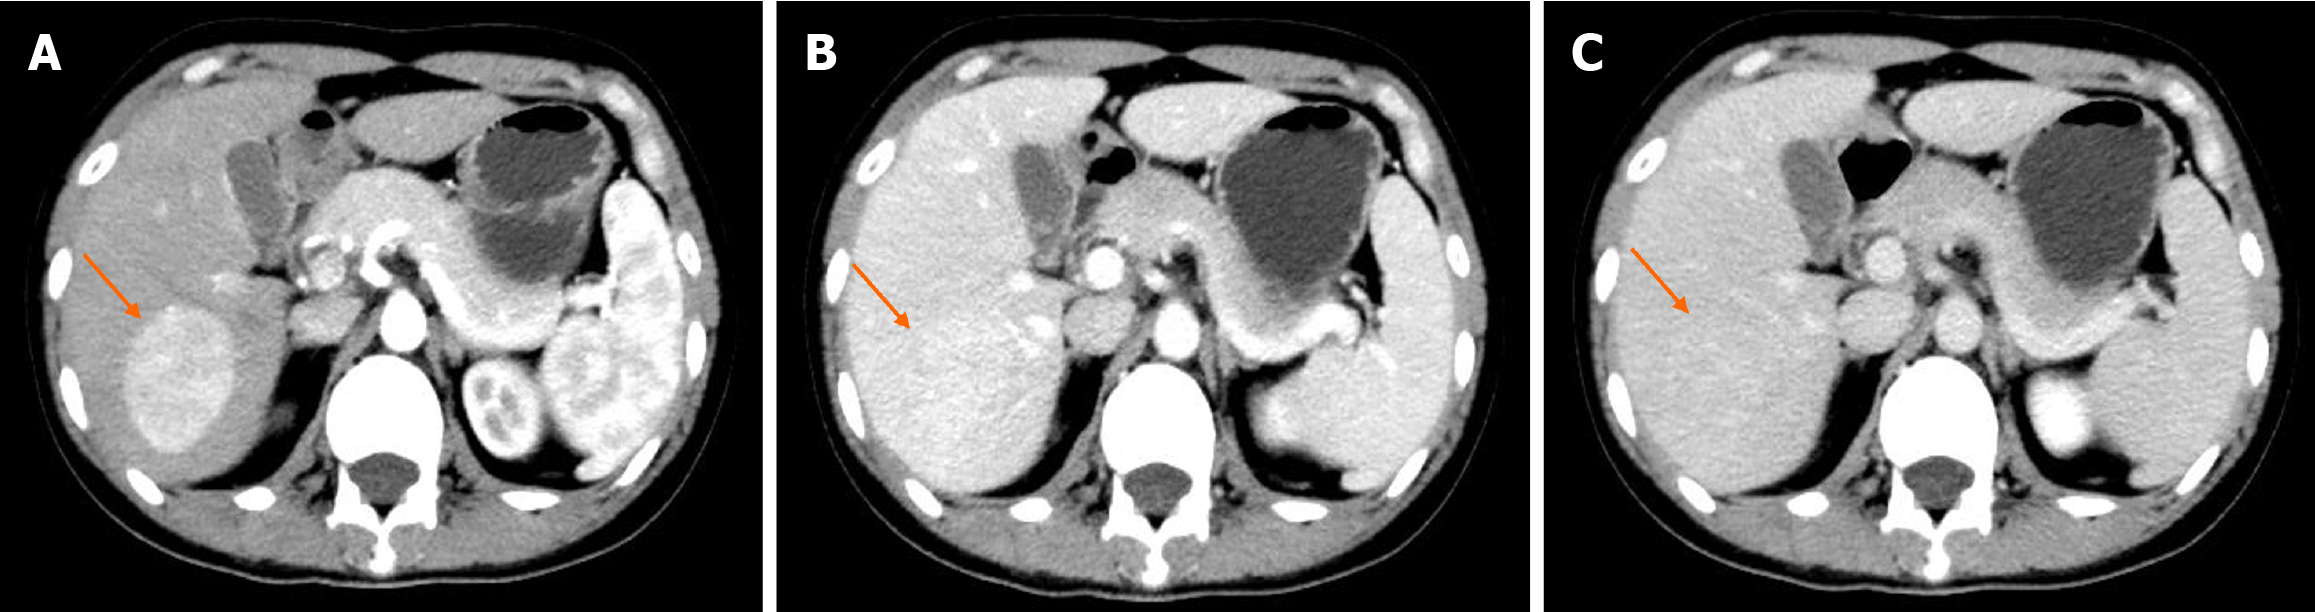

Figure 2 Images of the second contrast-enhanced computed tomography.

A: During the arterial phase, the lesion demonstrated heterogeneous enhancement, while the contrast agent was being washed out during the portal vein phase and delayed phase; B and C: Patchy low-density shadows.